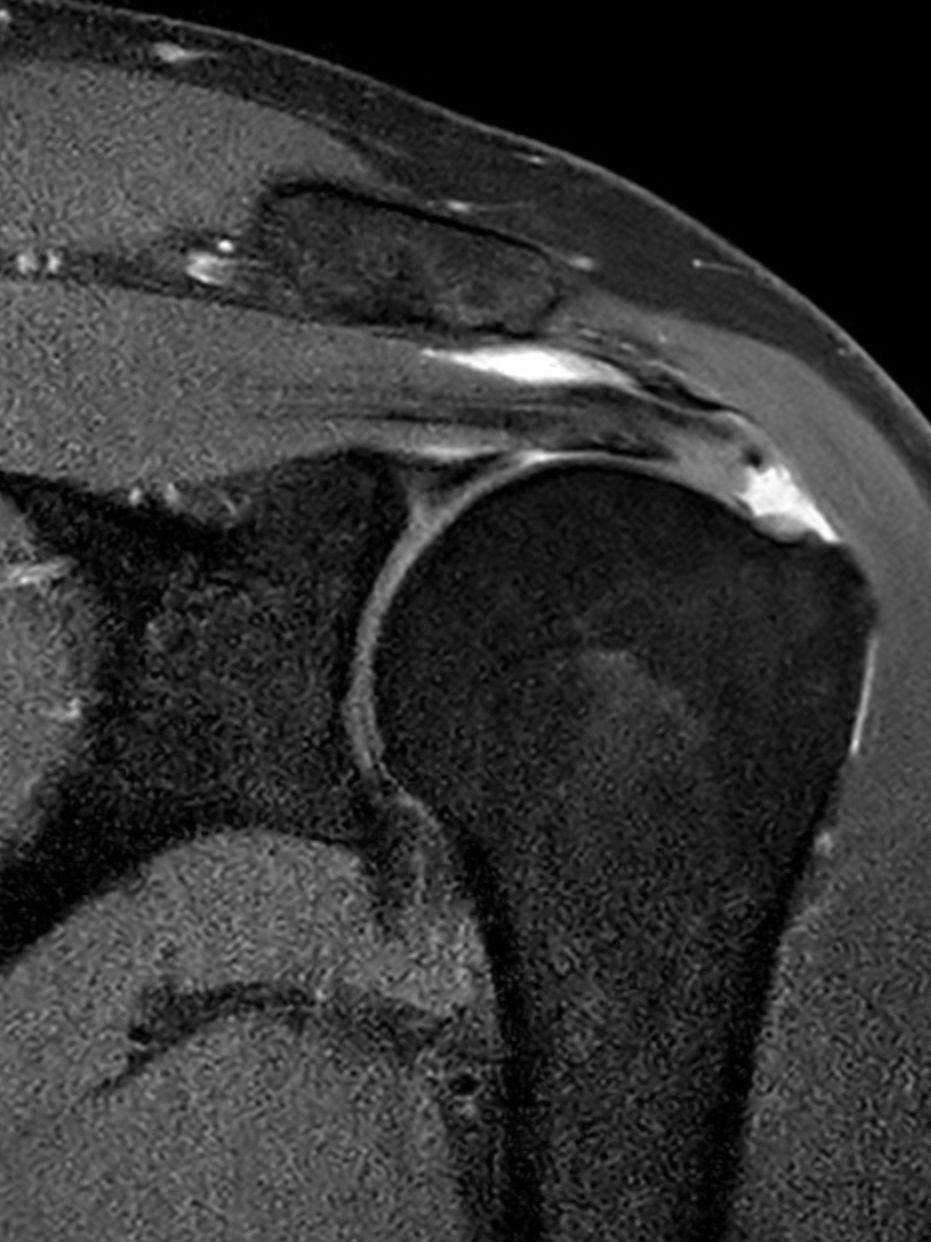

Rotator Cuff Tear

Calcific Tendinopathy